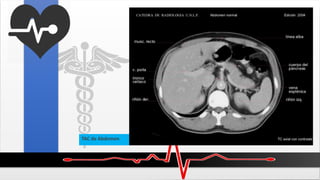

Estudios de imagen

 Radiografías en trauma abdominal

Rayos X de tórax PA:

Para excluir neumotoráx, hemotórax Y

neumoperitoneo.

Rayos X de Abdomen:

Examen Físico

Rayos X de pelvis

TAC de Abdomen